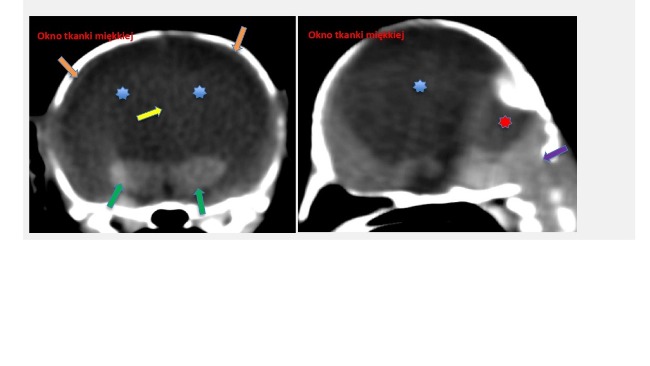

Poniżej opis tomografii komputerowej.